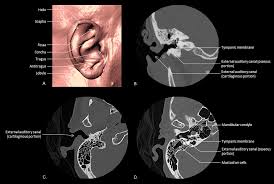

This structure helps to give each of us our unique appearance. The helicis minor is an oblique fasciculus, covering the crus helicis.; Supreet singh nayyar, afmc ms (ent) 2. Semicircular canals, vestibule, cochlea (see the image below){file12686} the ear is a multifaceted organ that connects the cen. The external ear (or outer ear) comprises the auricle (or pinna), the external auditory meatus, and the tympanic membrane (eardrum).

1 5 Times Human Ear Anatomy Model Showing Organs Structure Of The Central And External Ears Medical Teaching Supplies Medical Science Aliexpress from ae01.alicdn.com The medical term for the outer ear is the auricle or pinna. The external ear (or outer ear) comprises the auricle (or pinna), the external auditory meatus, and the tympanic membrane (eardrum). Semicircular canals, vestibule, cochlea (see the image below){file12686} the ear is a multifaceted organ that connects the cen. External ear (auricle) (see the following image){file12685} middle ear (tympanic): Supreet singh nayyar, afmc ms (ent) 2. The tragus, helix and the lobule. The external ear can be divided functionally and structurally into two parts; The tragicus is a short, flattened vertical.

The external ear can be divided functionally and structurally into two parts; The tragicus is a short, flattened vertical. Gralapp retain copyright for all of their original illustrations which appear in this online atlas. Diagnosis and management of foreign bodies in the outer ear. American academy of family physicians. The ear can be divided into three parts; The outer ear, external ear, or auris externa is the external part of the ear, which consists of the auricle (also pinna) and the ear canal. The auricle concentrates and amplifies sound waves and funnels them through the outer acoustic pore into the external auditory meatus to the tympanic membrane. It gathers sound energy and focuses it on the eardrum (tympanic membrane). Don't worry, though—each part has a purpose that is easy to understand. The intrinsic muscles of the external ear are: To request permission for publication or commercial use please. The helicis major is a narrow vertical band situated upon the anterior margin of the helix.it arises below, from the spina helicis, and is inserted into the anterior border of the helix, just where it is about to curve backward.;

External Ear from www.d.umn.edu There are three different parts to the outer ear; The outer ear, external ear, or auris externa is the external part of the ear, which consists of the auricle (also pinna) and the ear canal. External ear middle ear (cleft) inner ear 3. American academy of family physicians. The outer ear is made up of cartilage and skin. Malleus, incus, and stapes (see the image below) inner ear (labyrinthine): Semicircular canals, vestibule, cochlea (see the image below){file12686} the ear is a multifaceted organ that connects the cen. The helicis minor is an oblique fasciculus, covering the crus helicis.;

The helicis minor is an oblique fasciculus, covering the crus helicis.; The ear can be divided into three parts; Don't worry, though—each part has a purpose that is easy to understand. The intrinsic muscles of the external ear are: External ear anatomy (auricle or pinna) the outer ear auricle or external ear is composed of all of the parts of the ear outside the skull.

Otoscope Examination Physical Exam from www.ebmconsult.com The outer ear, external ear, or auris externa is the external part of the ear, which consists of the auricle (also pinna) and the ear canal. Semicircular canals, vestibule, cochlea (see the image below){file12686} the ear is a multifaceted organ that connects the cen. The ear can be divided into three parts; The helicis major is a narrow vertical band situated upon the anterior margin of the helix.it arises below, from the spina helicis, and is inserted into the anterior border of the helix, just where it is about to curve backward.; External ear anatomy (auricle or pinna) the outer ear auricle or external ear is composed of all of the parts of the ear outside the skull. The medical term for the outer ear is the auricle or pinna. This structure helps to give each of us our unique appearance. To request permission for publication or commercial use please.